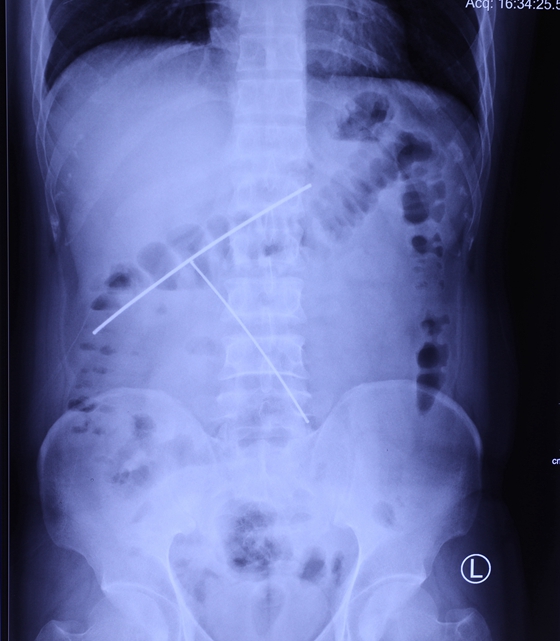

患者腹部X线影像

曾小明副主任医师接诊患者后,考虑异物存留体内四月余,恐有粘连,加之异物为细长钢丝,贸然行内镜下取异物极易造成穿孔、出血等并发症,遂将患者收治入院。入院后,湘雅常德医院消化内科主任张桂英教授及消化内科团队经仔细询问患者吞入钢丝的情况,细致的体格检查,分析X线及CT检查结果后,讨论制定异物取出方案,决定入院后第二天尝试行内镜下异物取出术。

据曾小明副主任医师介绍,由于两条相连的钢丝分别停留在胃与十二指肠之间及十二指肠水平部,位置较深,且钢丝嵌顿于胃壁及肠壁,消化内科内镜医护团队不得不采取“以退为进”的办法,在胃镜下看到钢丝后,先缓慢调整钢丝角度,使其顺应胃腔方向,然后尝试将两根钢丝皆推至胃腔,再谨慎取出。整个操作仅二十分钟,未伤及消化道壁,成功将两根连在一起长度超过30厘米的钢丝取出。